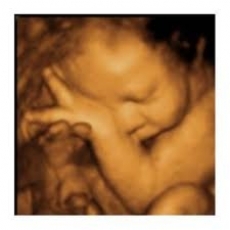

Dr MORARU PETRU     MEDIC PRIMAR OBSTETRICA GINECOLOGIE ATESTAT IN INFERTILITATE SI REPRODUCERE UMANA ASISTATA  FERTILIZARI IN VITRO .INSEMINARI ATESTAT IN ECOGRAFIE SARCINA ATESTAT HISTEROSCOPIE ATESTAT COLPOSCOPIE...

Consultatii obstetrica ginecologie Depistare si urmarire sarcina Ecografie  Colposcopie Interventii chirurgicale de obstetrica ginecologie Consultatii ORLEndoscopie si fibroscopie ORL Rhinoplastii Otoplastii Chirurgie ORLTelefon: 0257 273 8480745...

Consultatii de specialitate obstetrica - ginecologieExamen citobacterilogic vaginal PAPTratamente de specialitate obstetrica - ginecologieInterventii chirurgicale de obstetrica - ginecologie la Clinica Medlife (Genesys) AradNasteri la Clinca Medlife ...